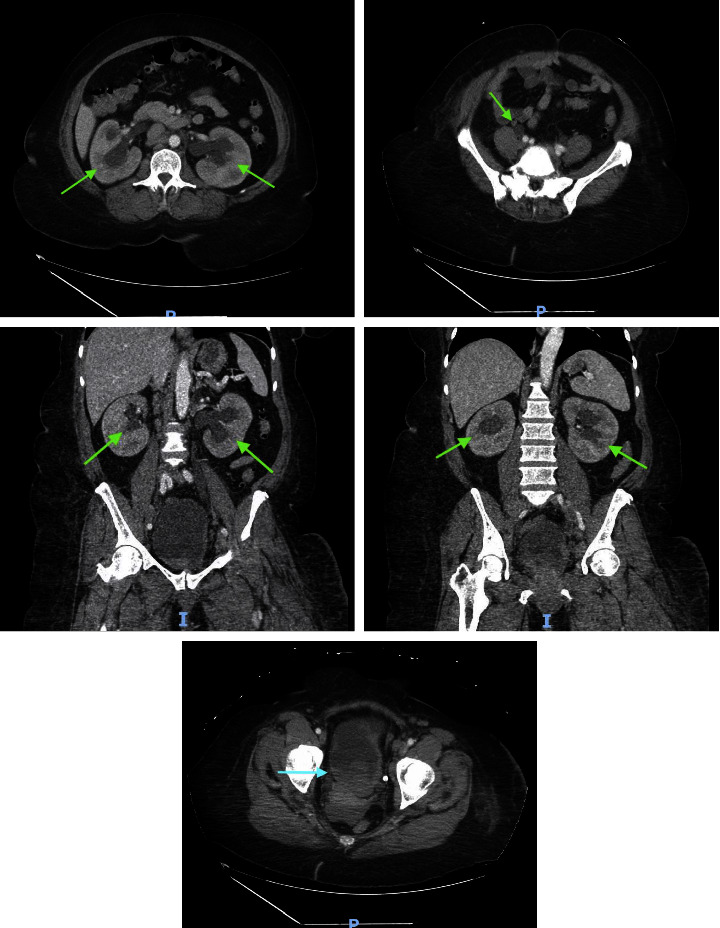

背景:目前,用于探讨癌症患者静脉血栓栓塞症构成的数据极少。本病例报告讨论了一名高级别尿路上皮癌患者的静脉血栓栓塞症状,并重点介绍了血栓的病理学发现。病例介绍。一名 55 岁的女性患者被诊断为高级别尿路上皮癌并有多处转移,左下肢出现广泛的深静脉血栓。由于左下肢疼痛和肿胀,抗凝治疗无效,因此需要进行血管内再通术。医生为她进行了机械性血栓切除术,并将样本送去进行病理检查。病理检查发现了微小的转移癌碎片,并混有层状血块(血栓)。转移癌的形态和免疫染色谱与膀胱转移癌相符:据估计,约有 4-20% 的癌症患者会在某个阶段出现 VTE,确诊后初期的 VTE 发生率最高。每年有 0.5% 的癌症患者会出现血栓,而普通人群的发病率为 0.1%(Elyamany 等人,2014 年)。尽管知道癌症患者的 VTE 发生率增加,但迄今为止分析癌症患者血栓组成的研究却很少。

Background: Currently, minimal data are available to explore the composition of venous thromboembolism in patients with cancer. This case report discusses a presentation of venous thromboembolism in a patient with high-grade urothelial carcinoma and highlights the pathology findings in thrombi. Case Presentation. A 55-year-old female who was diagnosed with high-grade urothelial carcinoma with multiple metastases developed an extensive deep vein thrombosis in her left lower extremity. Endovascular revascularization was indicated due to left lower extremity pain and swelling not responsive to anticoagulation. A mechanical thrombectomy was performed, and samples were sent for pathology. Pathologic examination discovered minute fragments of metastatic carcinoma, admixed with laminated blood clots (thrombus). The morphology of metastatic carcinoma and the immunostain profile were compatible with metastatic carcinoma of bladder origin.